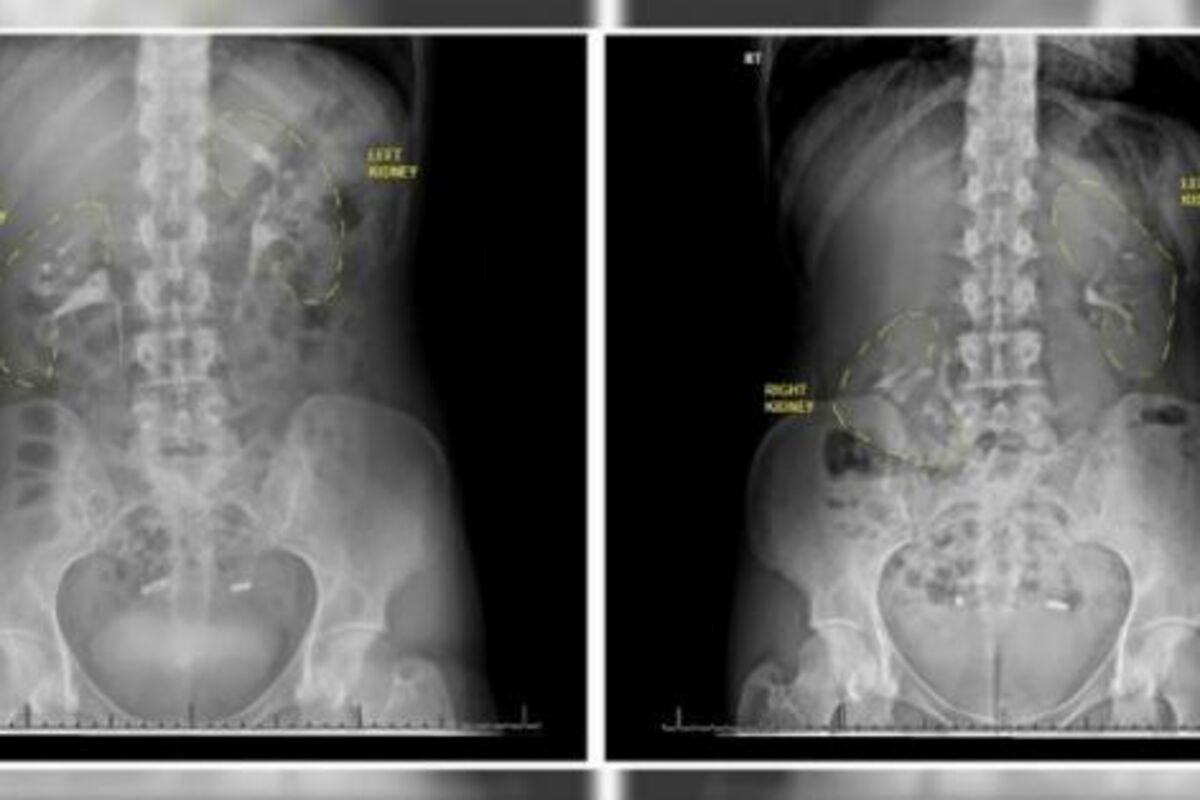

Žena je, naime, imala „lutajući bubreg“, odnosno nefroptozu, stanje u kome jedan od bubrega upadne u karlicu kada osoba ustane. Kod ove žene u pitanju je bio desni bubreg koji je stalno propadao više od šest centimetara.

– Jako je teško dijagnostikovati lutajući bubreg, inače vrlo retko stanje, uglavnom zato što, kada se radi snimanje, osoba leži pa je bubreg na svom mestu, pa lekari ni ne posumnjaju da tu leži problem – objašnjava on.